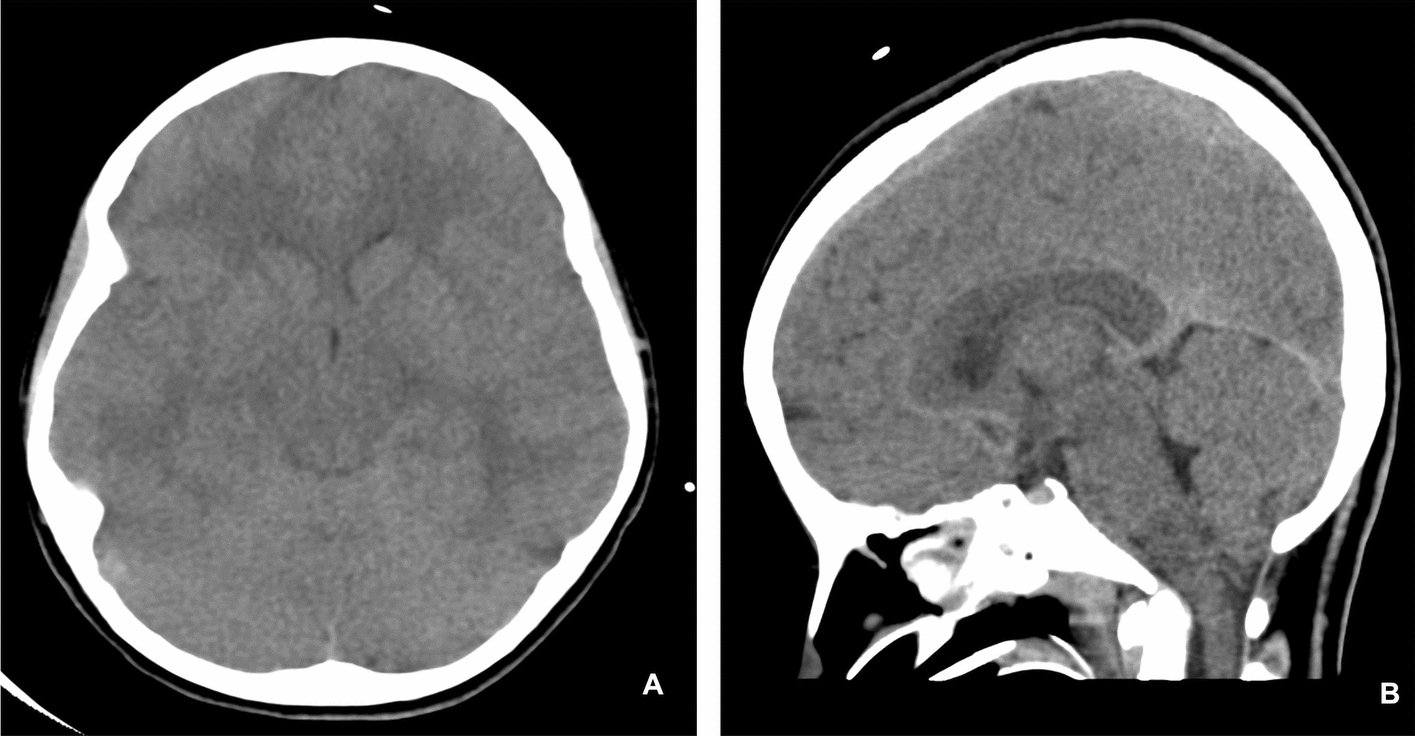

Case presentation: We report the case of a 12-year-old girl of Middle Eastern descent from Saudi Arabia with a history of bronchial asthma and allergic rhinitis who developed cerebral edema and resultant tonsillar herniation following a severe asthma exacerbation. Her presentation was marked by respiratory distress unresponsive to initial therapy. Intensive management in the pediatric intensive care unit including mechanical ventilation and neuroprotective measures resulted in full neurological recovery prior to discharge.